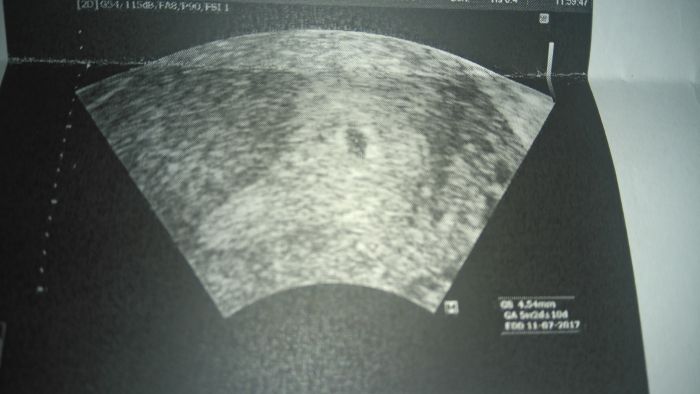

Tak holky je tam prcek :) 30.11 na krevni testy v 1.trimesteu a pro prukazku...

Iv: Moc gratuluji! Krasna ukazkova fotka a ze jsem jich nastudovala, kdyz jsem resila, co tam asi u me mohla videt za dutinu :-D.

přesně tohle jsem měla já na utz,ale na kontrolu jdu další koncem listopadu i když bych mohla za 14dni...